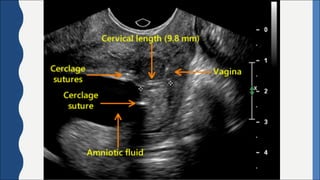

ULTRASONOGRAPHY

• Sonographic	measurement	of	cervical	length,	ideally	done	via	transvaginal

ultrasonography.

• A	short	cervical	length,	which	is	typically	defined	as	less	than	25	mm,	has	been

consistently	associated	with	an	increased	risk	for	preterm	birth.

• Cervical	effacement	appears	to	begin	at	the	internal	os	and	proceed	caudally.

• Preterm	birth	is	unlikely	to	occur	with	a	cervical	length	of	greater	than	30	mm.

Cervical	Cerclage:

• Placement of a stitch in an attempt to improve the tensile strength of the cervix.

• A cerclage can be placed from a transvaginal or transabdominal approach, with the

primary objective of reinforcing the cervix at the level of the internal os and, thus,